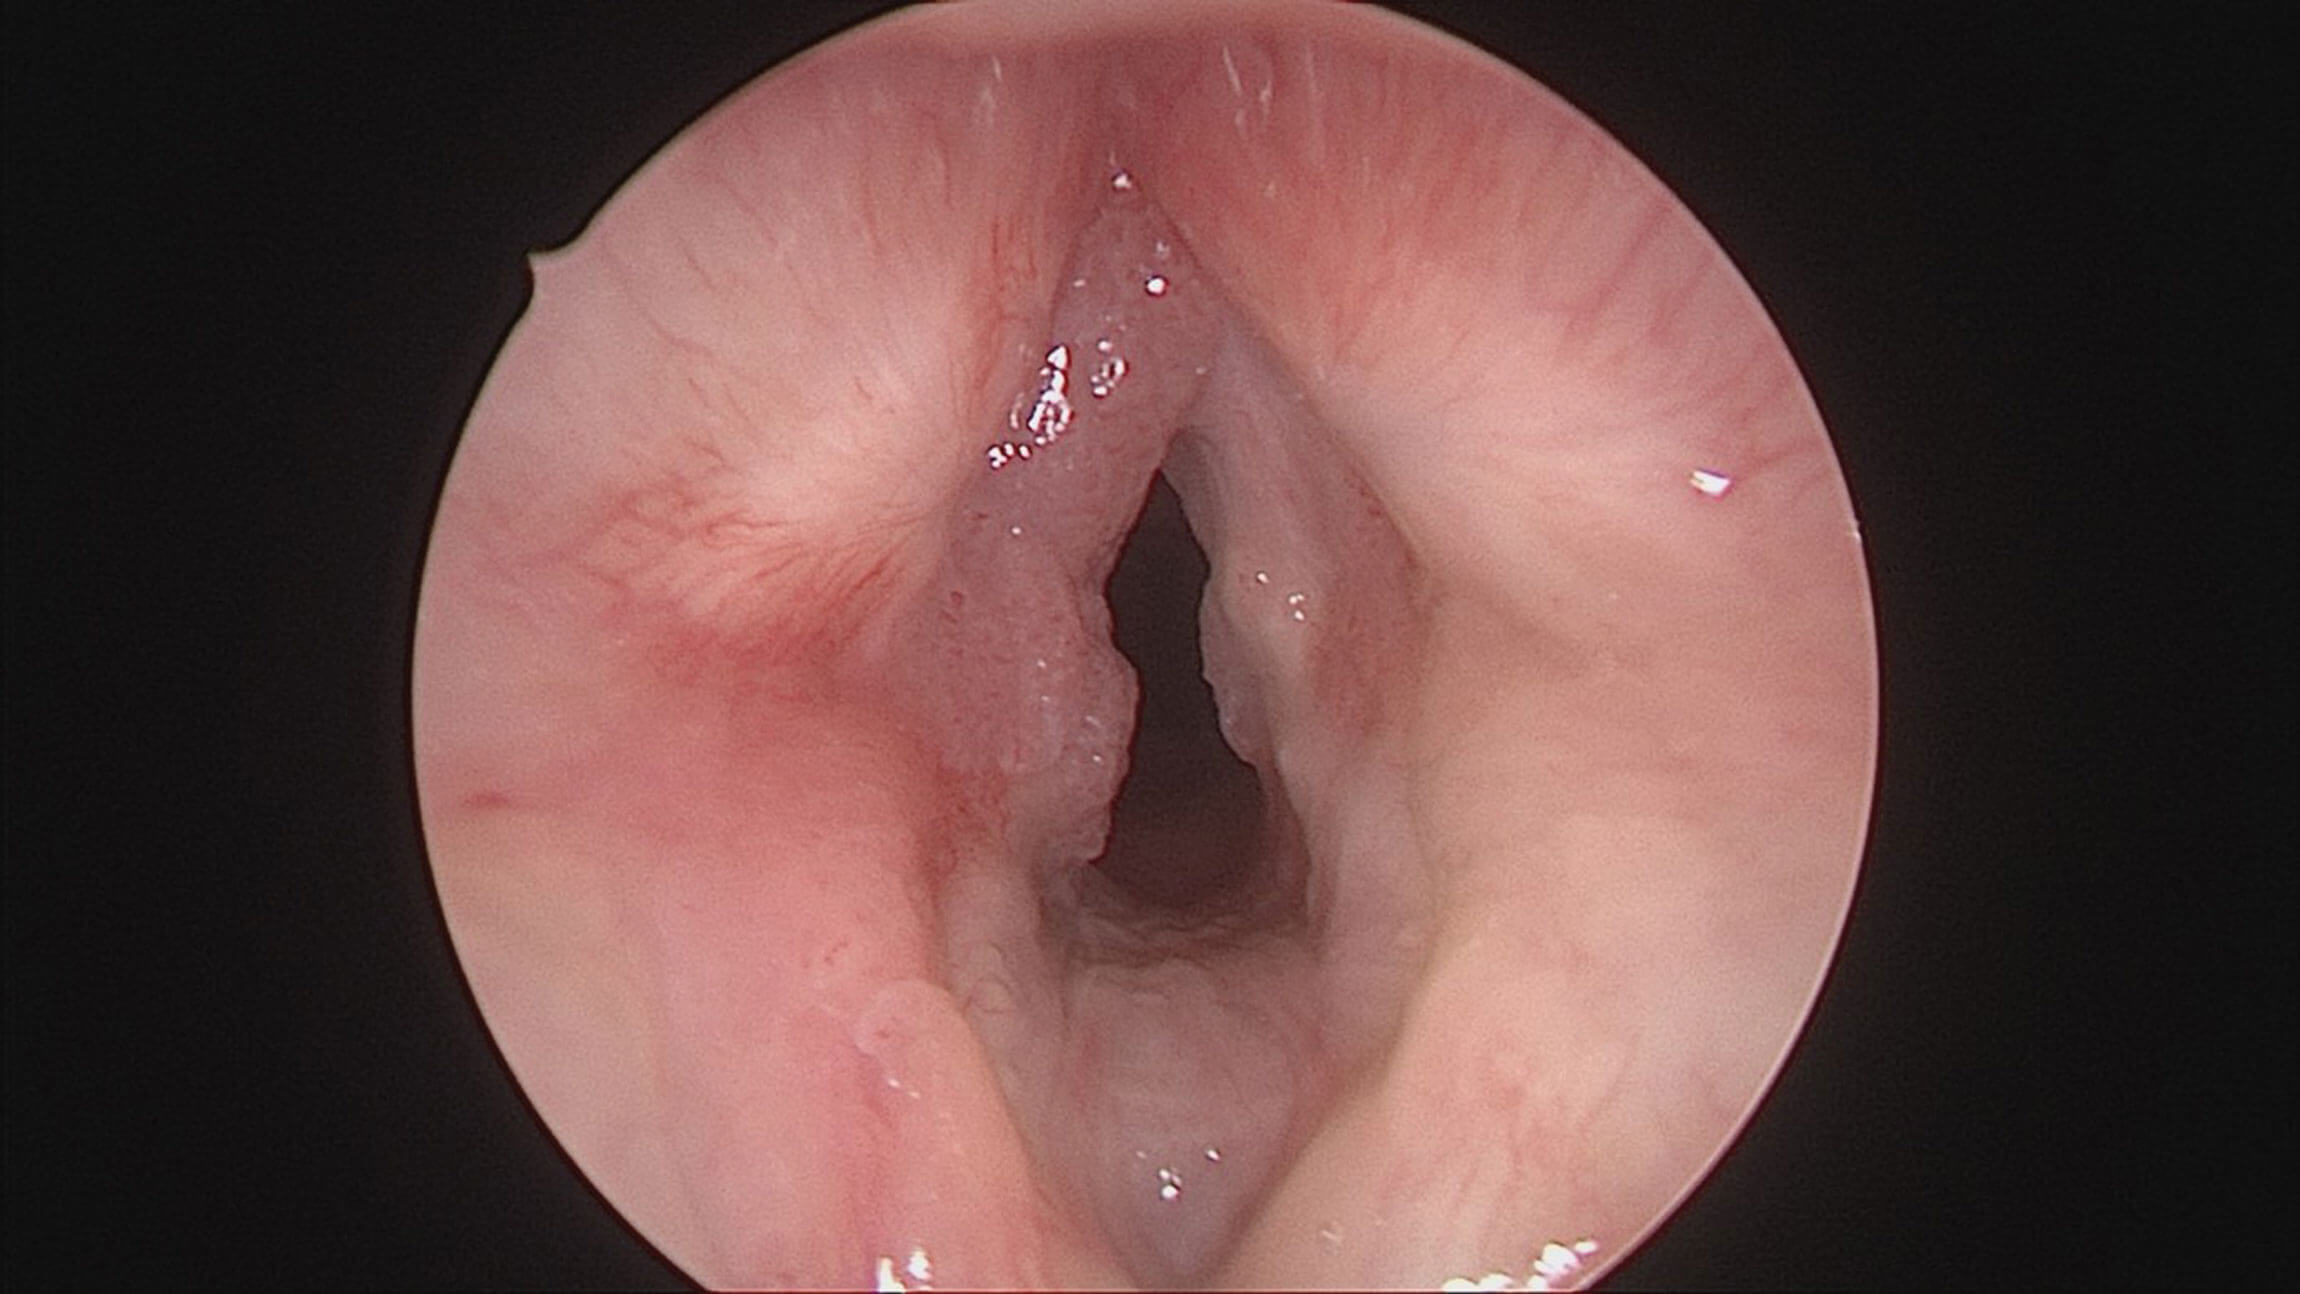

Figure 2. Endoscopic view of larynx showing recurrent respiratory papillomatosis.

Microdebrider

The microdebrider has had a number of applications in ENT and is now commonly used in the sinus and larynx. The laryngeal microdebrider with a skimmer blade is rapidly becoming the modality of choice for recurrent respiratory papillomatosis (RRP). As opposed to the CO2 laser, it is associated with less damage to the normal surrounding tissue, leading to less scarring. Endoscopic visualisation allows for accurate targeting of diseased tissue.